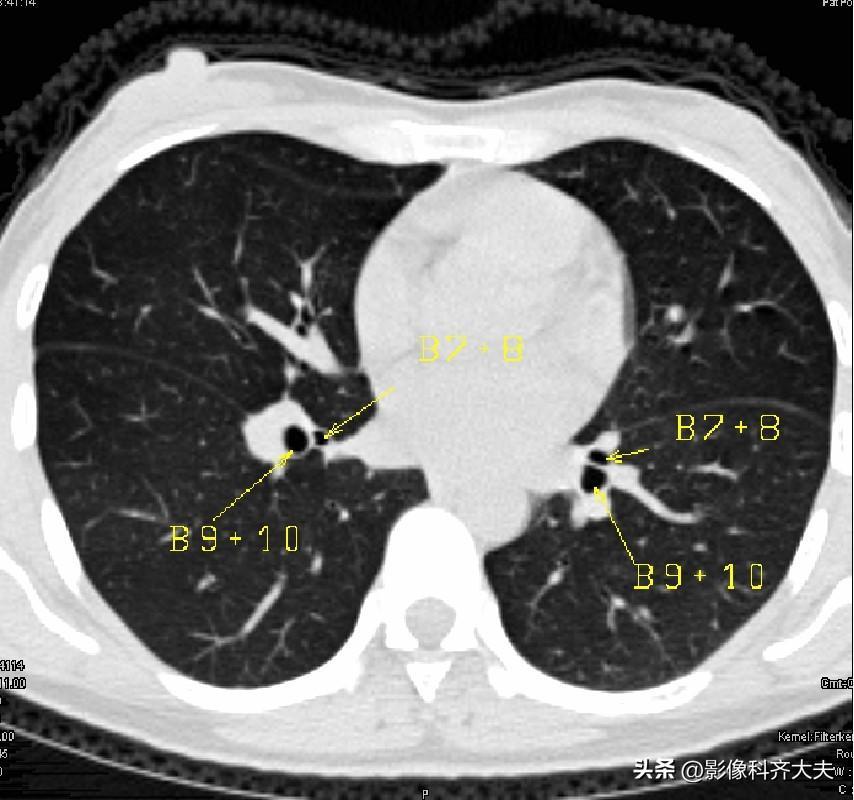

图15-近心底层面

▲B7+8:下叶前内段支气管

图16-近心底层面

▲B7:下叶内段支气管,B8:下叶前段支气管,B9:下叶外段支气管,B10:下叶后段支气管